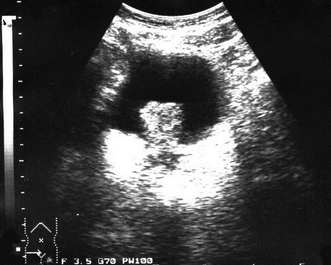

Выявление гиперэхогенного очага в полостной системе свидетельствует о конкременте (рис. ниже) или разрастании патологической ткани (рис. ниже) При наличии конкремента за ним определяется эхонегативная полоска – «дорожка», или «акустическая тень», которая отсутствует позади опухоли.

Сонограмма желчного пузыря с множеством конкрементов (пояснения см. в тексте).